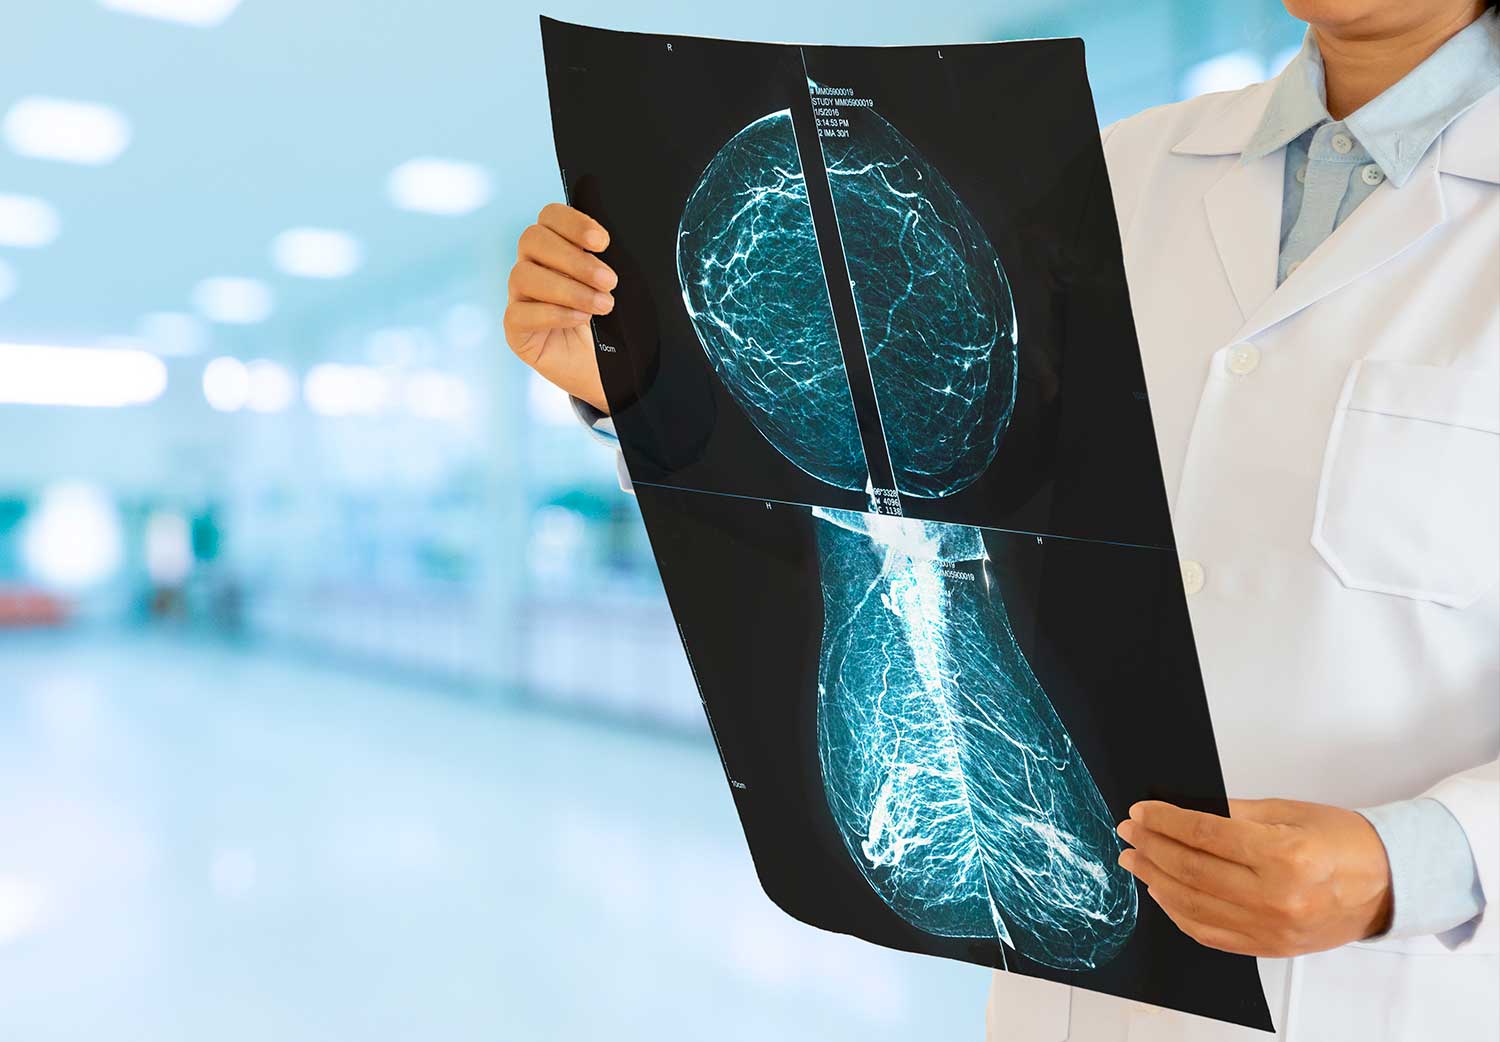

Sobre la Mastografía

La mamografía es el ÚNICO método de imagen que ha demostrado disminución en la mortalidad por cáncer de mama de un 29 a 30% en la población tamizada.

O sea, permite un diagnóstico temprano, SIEMPRE Y CUANDO se haga con periodicidad y un estricto control de calidad.

La mamografía debe hacerse posterior al término del ciclo menstrual (7 días después), en centros de imagen mamaria que tengan la tecnología adecuada como:

Mastografos digitales con pantallas de alta resolución de uso médico.

Médicos radiólogos certificados por el Colegio Americano de radiología con calificación adicional en imagen mamaria los cuales tengan experiencia para interpretar dichos estudios.

La interpretación debe seguir ciertos parámetros establecidos por el Colegio Americano de Radiología, en donde al final se debe dar de forma OBLIGADA una clasificaciónn del BIRADS (breast imaging reporting and data system).

Usar pantallas de alta resolución de uso médico han permitido identificar carcinomas milimétricos antes imposibles de identificar.

Mastógrafo digital

Paleta de mínima compresión

Transductores

Pantalla de alta resolución

Mastografía que muestra microcalcificaciones

pleomorficas de alta sospecha de malignidad